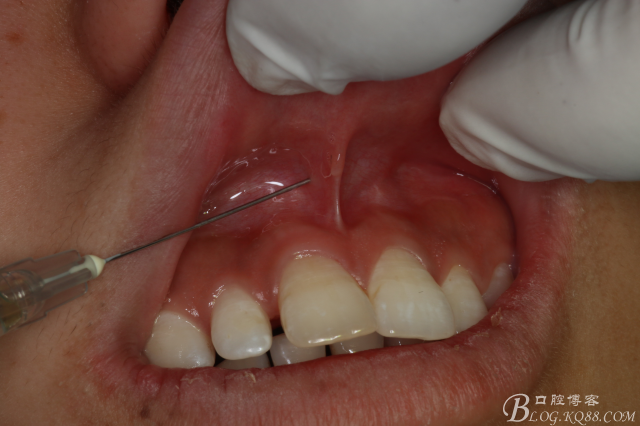

圖1.患者術(shù)前的口內(nèi)正面像:11和21前突、11和12有間隙

圖5.唇、腭側(cè)局部無(wú)痛浸潤(rùn)麻醉